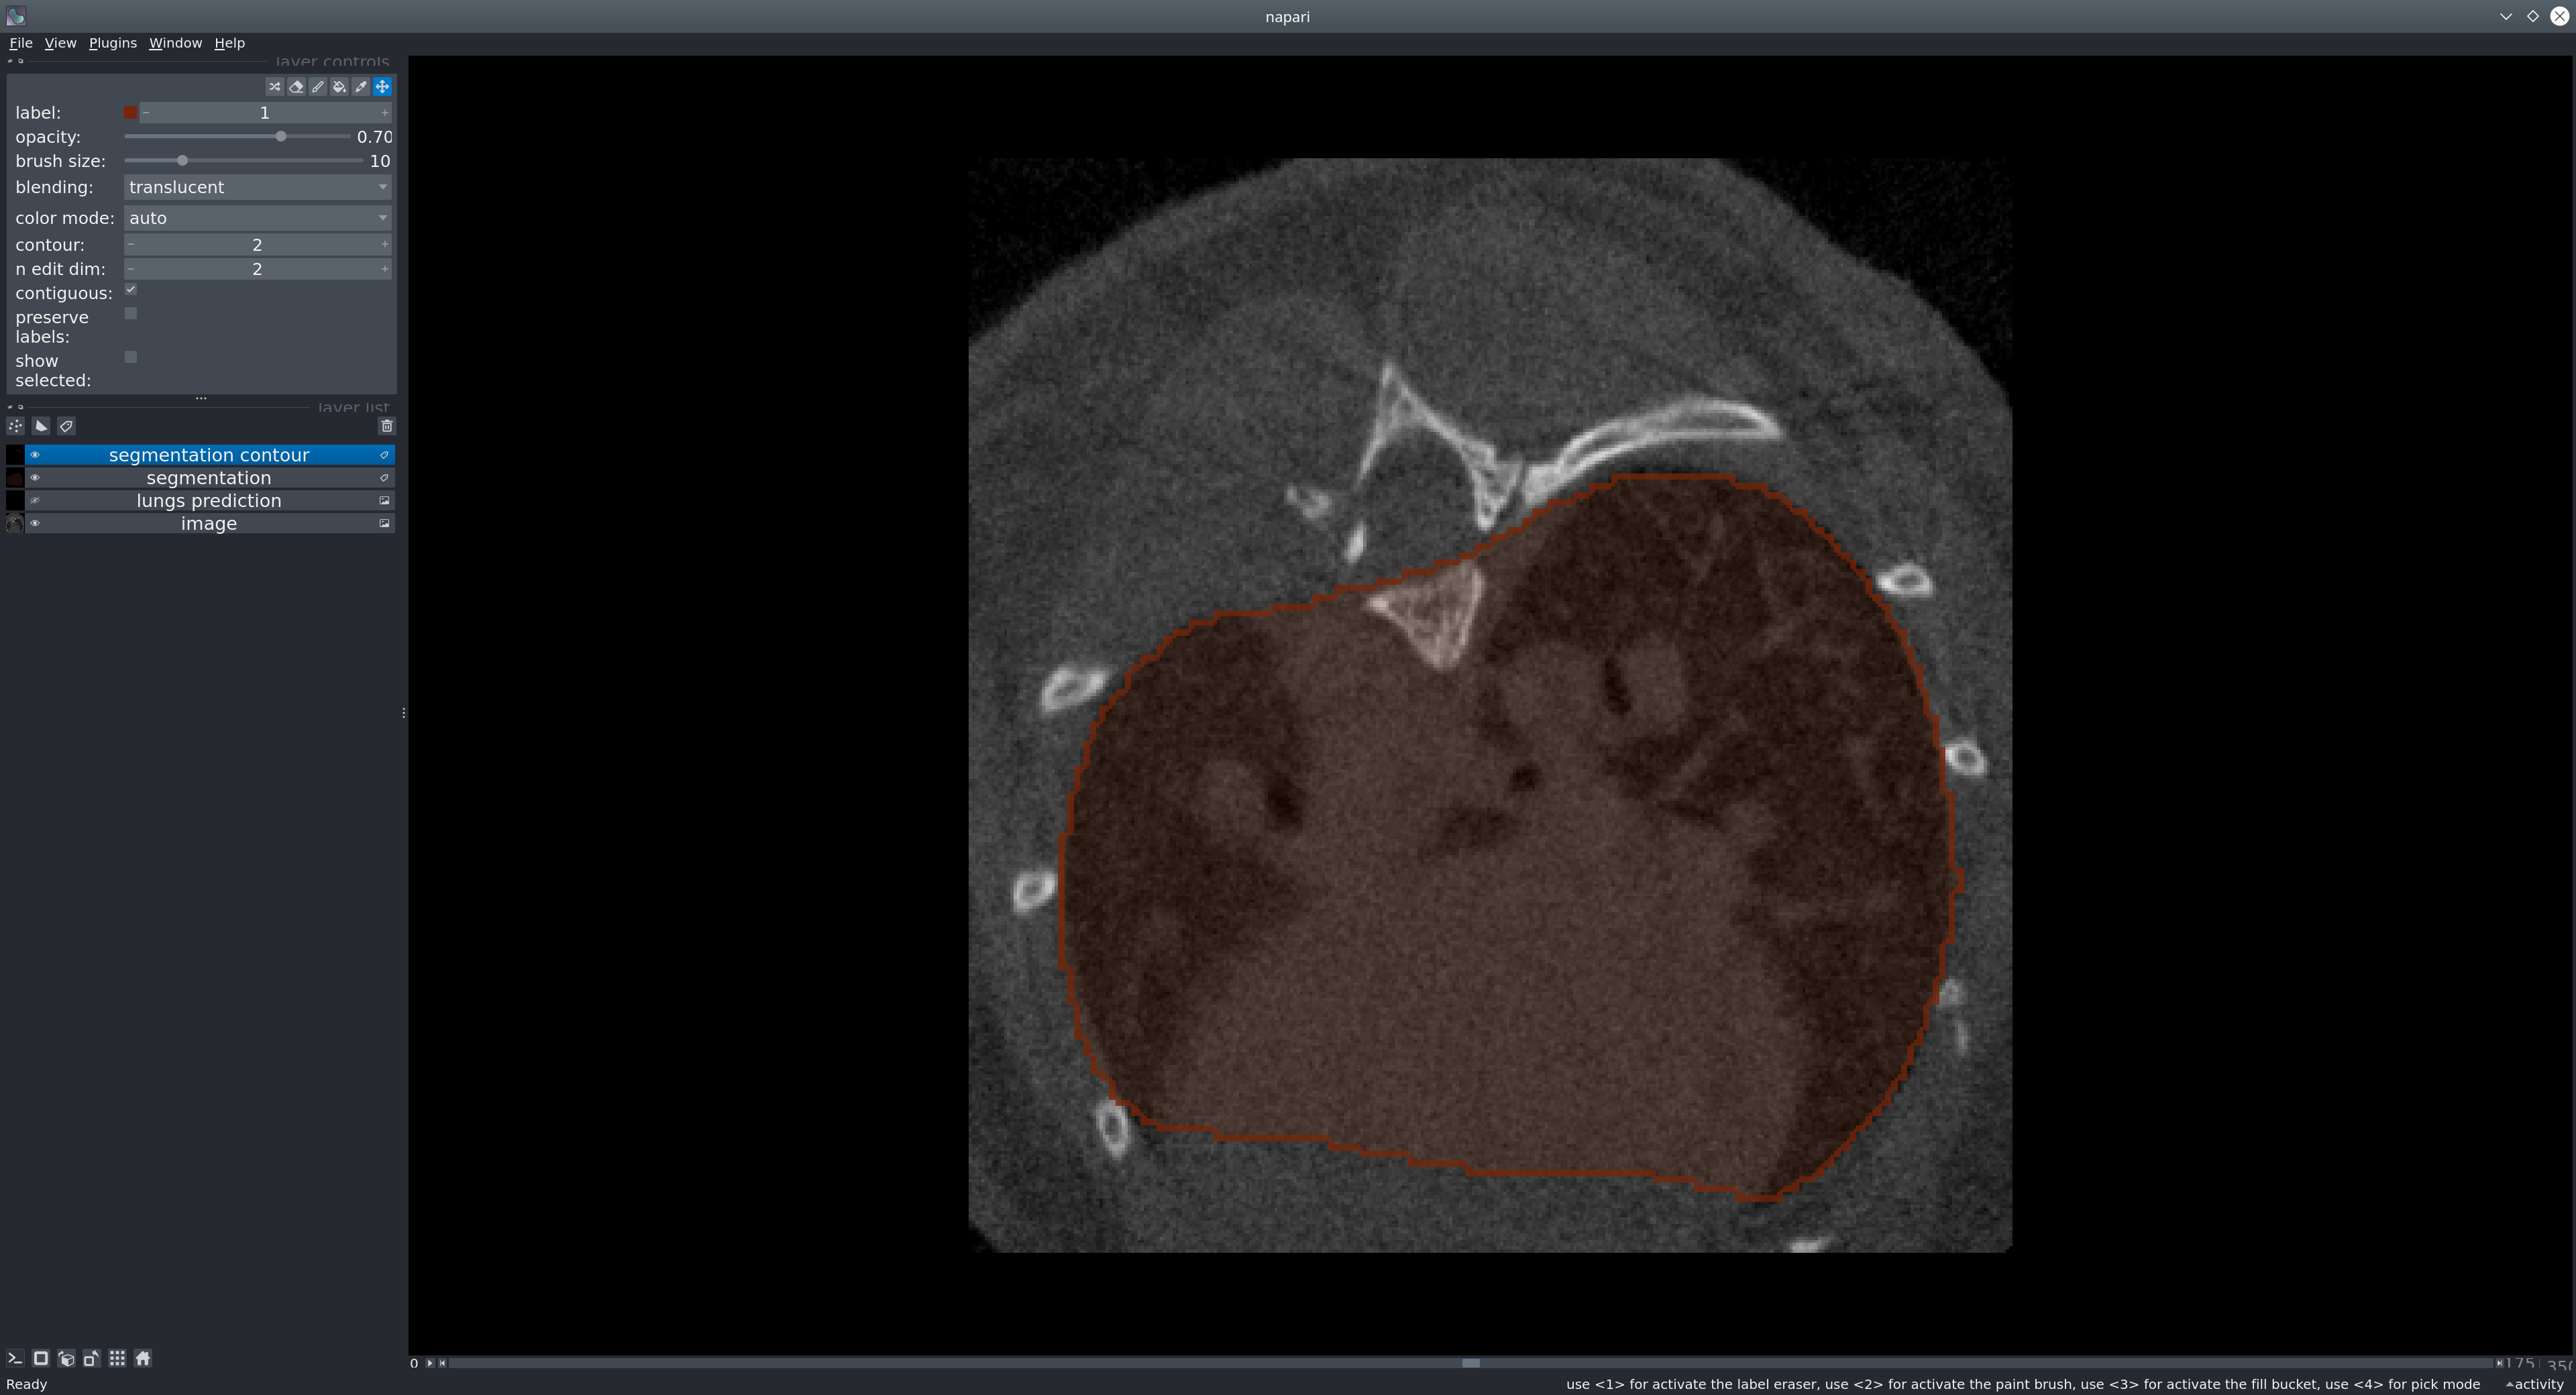

3D U-Net model for the segmentation of the lungs in mice CT scans.

We provide a neural network model for segmenting the lungs of the mice. The model is based on the U-Net architecture.

The goal of our tool is to provid a reliable way to segment the lungs in mouse CT scans. The U-net model produces a binary mask representing the segmentation of the lungs.

Usage in Napari

Napari is a multi-dimensional image viewer for python. To use our model in Napari, start the viewer with

Sample data: To test the model, you can run it on our provided sample image. In Napari, open the image from File > Open Sample > Mouse lung CT scan.

Next, in the menu bar select Plugins > Lungs segmentation (unet_lungs_segmentation). Select an image and run it by pressing the "Segment lungs" button.